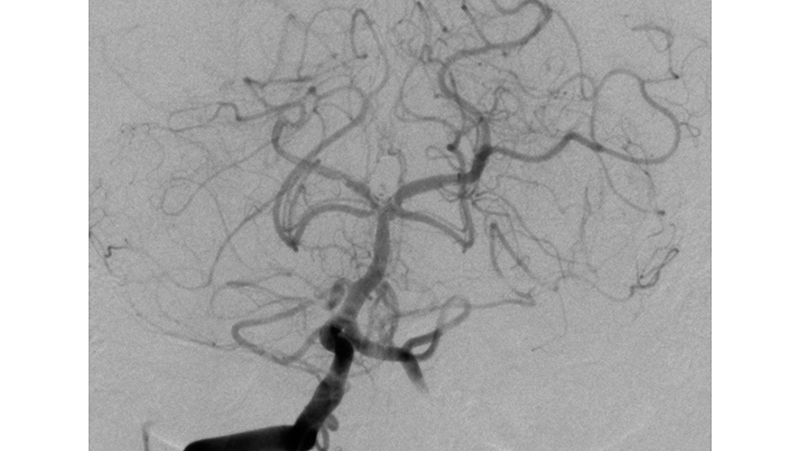

Εικόνα 3: Όπως φαίνεται το εύρος του αυχένα είναι 6 χιλιοστά.